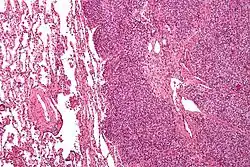

| Micrograph of metastatic Ewing sarcoma (right of image) in normal lung (left of image). PAS stain. | |

Ewing sarcoma is a small-blue-round-cell tumor that typically has a clear cytoplasm on H&E staining, due to glycogen. The presence of the glycogen can be demonstrated with positive PAS staining and negative PAS diastase staining. The characteristic immunostain is CD99, which diffusely marks the cell membrane. However, as CD99 is not specific for Ewing sarcoma, several auxiliary immunohistochemical markers can be employed to support the histological diagnosis.[23] Morphologic and immunohistochemical findings are corroborated with an associated chromosomal translocation, of which several occur. The most common translocation, present in about 90% of Ewing sarcoma cases, is t(11;22)(q24;q12),[24][25] which generates an aberrant transcription factor through fusion of the EWSR1 gene with the FLI1 gene.[26]